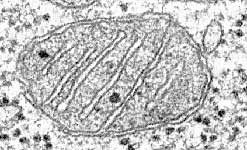

Mitochondrial DNA

Mitochondrial DNA has recently been linked to a range of illnesses from chronic brain disease in children to high blood pressure later in life.

Now scientists at Newcastle University hope that implanting the nucleus of an embryo with defective mitochondria, into an egg from another woman could stop these diseases from being inherited. Syndrome X